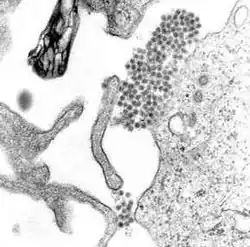

![]() Micrografía de microscopio electrónico mostrando el virus causante de la fiebre hemorrágica del dengue | ||

El dengue es producido por un virus del grupo de los arbovirus (llamados así porque son transmitidos a través de artrópodos hematófagos), familia de los Flaviviridae, género Flavivirus. La partícula viral tiene forma esférica y mide entre 30 y 50 nm. Posee una envoltura proteica (principalmente E y M) que la cubre por completo. El material genético se encuentra contenido en un nucleocápside circular, y entre este y la cubierta se encuentra una bicapa lipídica que es formada a partir de lípidos extraídos de la membrana celular de la célula huésped. El genoma se compone de una sola cadena de ARN de tipo lineal, sentido positivo y gran variabilidad. El virus es altamente inestable en el medio ambiente, inactivándose con el calor, desecación y desinfectantes que contengan detergentes o solventes lipídicos.

El virus del dengue, al igual que otros flavivirus, contiene un genoma de ARN rodeado por una nucleocápside de simetría icosaédrica, de 30 nm de diámetro, la cual está constituida por la proteína C ―de 11 kd― y una envoltura lipídica de 10 nm de grosor asociadas a una proteína de membrana (M) y otra de envoltura (E), que da lugar a las proyecciones que sobresalen de la superficie de los viriones.[31]